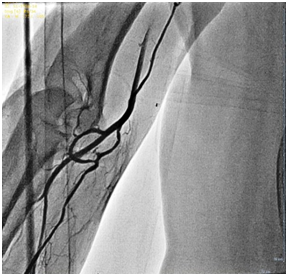

RAA are relatively common in general population, although there are limited data concerning this issue worldwide [4]. Their incidence may vary according to the available literature, starting from 8,8% [7,6], 13,8% [2], up to 22,8% according to Valsecchi et al. [3]. They can be reason for procedural failure in 1-5% of the patients even in experienced operators` hands [4,9]. RAA include high bifurcating origin of the radial artery (high take-off radial artery) (Figure 1), radial artery loop (Figure 2 & 3), tortuosity (Figure 1), hypoplasia and stenosis. In most cases, these anomalies can be overcome by using hydrophilic guiding wire and diagnostic 5F Judkins right catheter (JR 4) or even 4F Judkins right catheter, sometimes 0,014” hydrophilic coronary wire [1] and in rare cases by using so-called BAT technique (“balloon-assisted tracking”), a technique proposed by Dr. Tejas Patel et al. [9]. Operators should be experienced in TRA and by using some simple maneuvers like push-and-pull technique and catheter rotation usually achieve a successful negotiation with the radial artery (Figure 4).

Figure 1: High-take off tortuous radial artery.

Figure 2: High-take off tortuous radial artery.